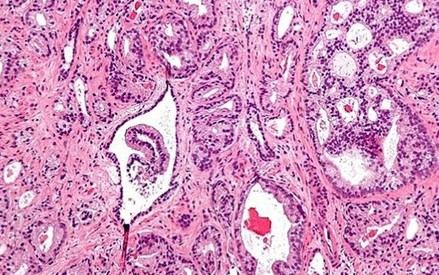

Un estudio del Instituto de Salud Carlos III revela que la exposición al arsénico está asociada con un mayor riesgo de desarrollar cáncer de próstata avanzado en hombres. El análisis, basado en datos de más de 800 varones, muestra que aquellos con niveles elevados de arsénico en las uñas tienen casi el doble de probabilidad de padecer esta enfermedad, especialmente en sus formas más agresivas. Este hallazgo subraya la importancia de controlar la presencia de arsénico en el agua potable y el entorno para reducir riesgos para la salud pública.